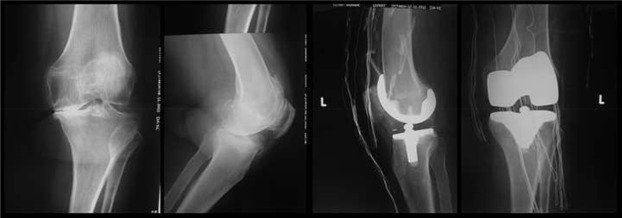

A 67-year-old woman was admitted to the outpatient clinic with complaints of left foot and ankle pain, swelling, limitation of motion and difficulty in weight bearing and walking. The patients history revealed a left TKA operation two months prior, and complaints started at the first month postoperatively (Fig. 1 ). Nonsteroidal anti-inflammatory drug (NSAID) failed to relieve the pain, swelling, and tenderness and these symptoms had gradually increased. The patient reported that she could not wear socks or shoes and could not walk without a cane due to pain. She described the pain as burning, numbness, and pins and needles sensations. Her sleep was also disturbed. The medical history of the patient included hypertension and a surgical procedure for cystocele.

Preoperative and postoperative radiographs of the left knee.